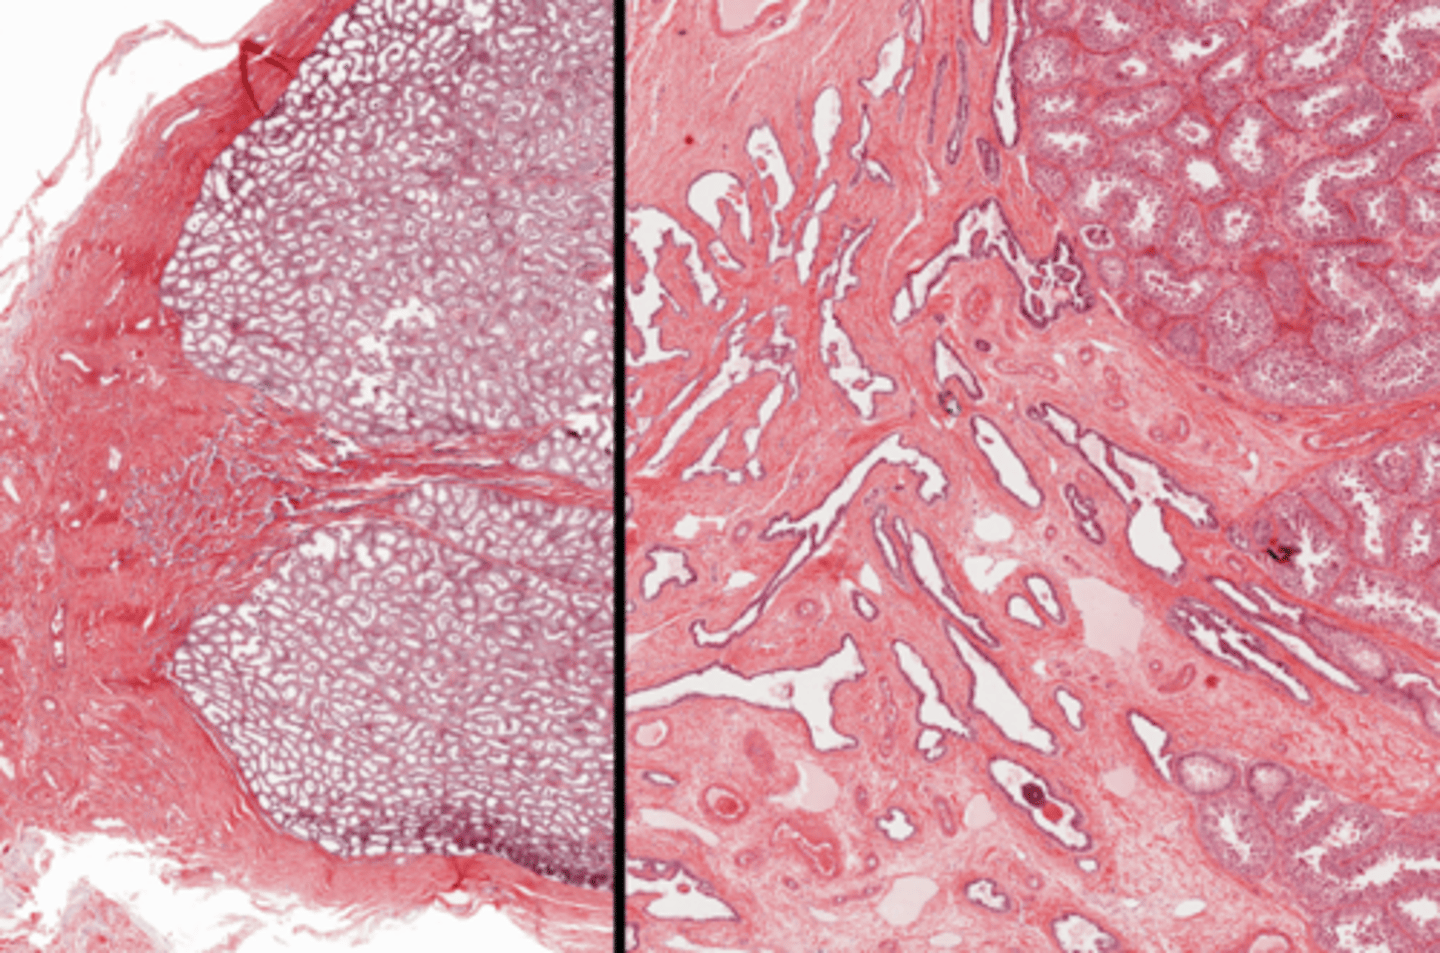

Penis (juvinile)

Penis (post-pubescent)

Erectile tissue

Corpus cavernosum

Corpus spongiosum